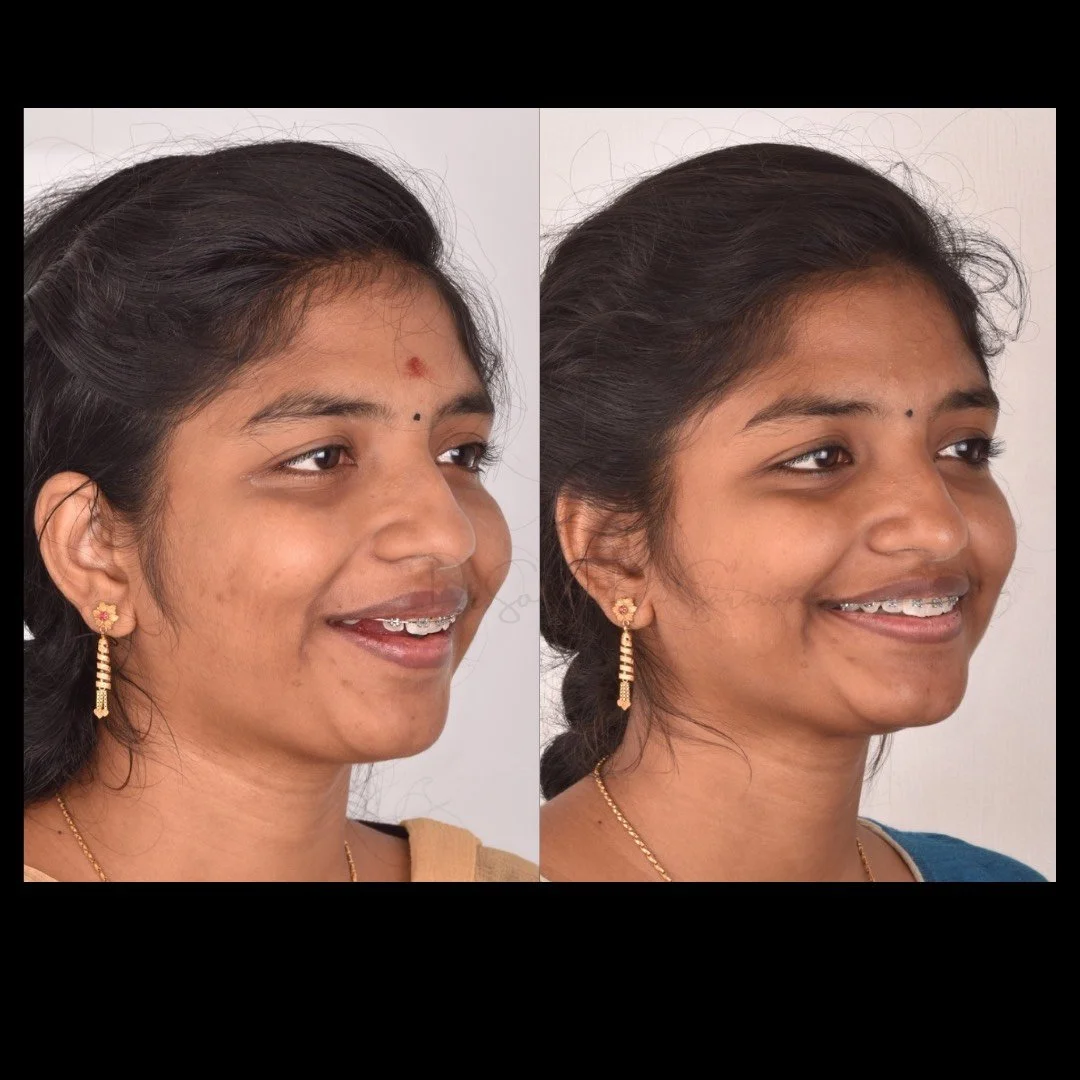

smile makeover

Smile Journey!

May be it is too simple to treat but the way this smile makeover made a difference in her life is immense! thats how wonderful smile curves are created!